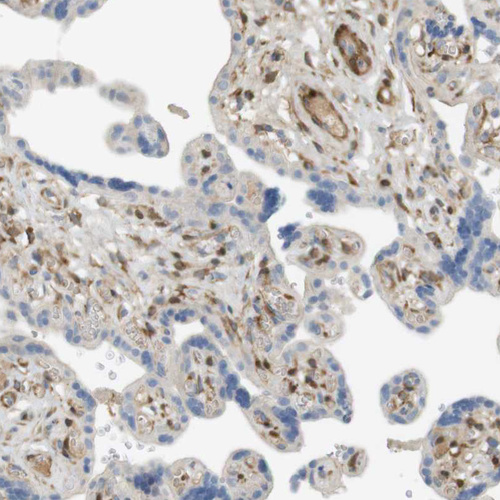

Learn how we validate our antibodies, how we secure their reproducibility, and why we apply enhanced validation. Our antibodies are validated in IHC, ICC-IF, and WB.